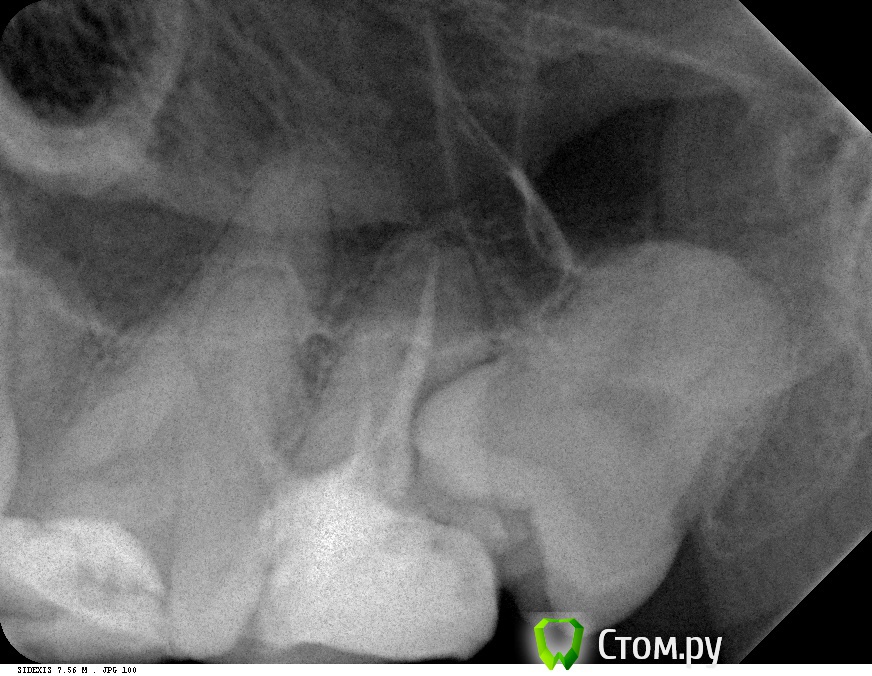

pacient7 Опубликовано 12 апреля, 2014 Автор Поделиться Опубликовано 12 апреля, 2014 Имхо надо сделать прицельный снимок в области верхних левых 7 и 8 зубов , а потом - решать.Вот прицельный снимок верхних левых 7-го и 8-го (снимок сделан два месяца назад, сразу после этого 8-ой зуб был удален). Ссылка на комментарий

samsonov Опубликовано 12 апреля, 2014 Поделиться Опубликовано 12 апреля, 2014 Вот прицельный снимок верхних левых 7-го и 8-го (снимок сделан два месяца назад, сразу после этого 8-ой зуб был удален).Значит нужен снимок седьмого после удаления. 1 Ссылка на комментарий

pacient7 Опубликовано 14 апреля, 2014 Автор Поделиться Опубликовано 14 апреля, 2014 (изменено) Значит нужен снимок седьмого после удаления.Сделал снимок 27-го верхнего левого зуба, как Вы просили. Присоединил. Зуб реагирует болью на нажатие (так же как и нижние 36-ой и 37-ой). Эндодонтолог говорит, что по его мнению все боли из-за этого зуба, и его надо эндодонтически перелечивать или удалять. Но зная предысторию о том, что лечение нижних зубов боль не купировало, а только усугубило проблемы с ВНЧС, я сильно колеблюсь, лечить ли 27-ой. Что скажете?http://s32-temporary-files.radikal.ru/da87dfeeb7834aae9a56c4f869f7980b/-88693455.jpg Изменено 14 апреля, 2014 пользователем pacient7 Ссылка на комментарий

samsonov Опубликовано 14 апреля, 2014 Поделиться Опубликовано 14 апреля, 2014 Помимо проблем с каналами седьмого зуба , возможно, есть дефект корня . Т. о. , не исключается вариант удаления. 1 Ссылка на комментарий

Skip Опубликовано 14 апреля, 2014 Поделиться Опубликовано 14 апреля, 2014 Скажите пожалуйста, по поводу "повреждения периакальной области", это Вы о каком зубе? И как с ним быть? Вот это имелось ввиду и коллега, в другой теме, тоже обратил Ваше внимание к этому: http://i6.pixs.ru/storage/8/5/9/15f08af62c_1214000_11696859.jpg Расширение апикального отверстия при пульпитах и уж тем более выход за верхушку корня всегда будет сопровождаться болезненностью после обтурации. А на холод, скорее всего, реагирует 5-ка кариозная. По поводу ВНЧС, какое Вы рекомендуете лечение в таком случае? Шина? В начале всей этой истории я пробовал aqualyzer (http://www.aqualizer.com), и он мне помогал. Первый челюстной ортопед у которого я был педлагал сделать пластиковую шину которую надо одевать на ночь (если удаление зуба не поможет), типа такой по внешнему виду: Если с aqualyzer становилось лучше, то это хороший диагностический признак того, что положение нижней челюсти, а вместе с ней и суставов, играет здесь первую скрипку. Это такое лечение как Вы имеете в виду? Лечения не может быть без диагноза, а следовательно, необходимо провести обследование, как клиническое, так и рентгенологическое, имея ввиду ВНЧС.Просто засунув Вам в рот шину, не понимая, что присходит в суставе, ни к чему хорошему не приведёт. Здесь необходима стратегия в выборе аппарата. 2 Ссылка на комментарий